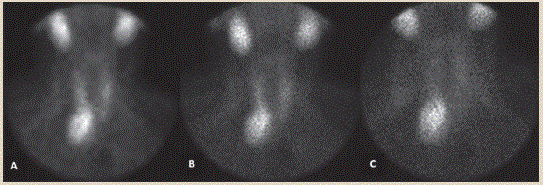

Cuando se realizó el diagnóstico y ante la sospecha de un adenoma paratiroideo como la causa del padecimiento, se envió a la paciente a nuestro servicio para su valoración, por lo que solicitamos una gammagrafía tiroidea/paratiroidea con 99mTc sestaMIBI (figura 3) reportada con biodistribución normal del radiofármaco en fase tiroidea y persistencia de una zona focal de la concentración localizada en topografía de polo inferior del lóbulo tiroideo derecho. Se complementó dicho estudio con SPECT-CT, donde se reportó imagen de paratiroides inferior derecha hiperfuncionante compatible con adenoma (figura 4). Se diagnosticó a la paciente con HPTP causado por adenoma paratiroideo gigante. Por lo tanto, se programó la cirugía para las semanas siguientes, en las cuales se realizó resección de adenoma paratiroideo inferior derecho, de aproximadamente 7.0 × 4.5 × 2.0 cm. A su vez, se llevó a cabo un estudio transoperatorio por el servicio de Anatomía Patológica, la biopsia fue informada como adenoma paratiroideo donde se pudo observar una estructura homogénea de células principales, irregularmente ovoide con un peso de 24.5 g (figura 5).

Figura 3 SPECT-CT con imagen nodular de 30.0 × 27.8 × 59.2 mm en cortes transversal, sagital y coronal respectivamente, donde se reporta imagen de paratiroides inferior derecha hiperfuncionante posterior al lóbulo tiroideo inferior derecho con extensión a la porción superior de mediastino, el cual desplaza la vía aérea hacia la izquierda. Imagen compatible con adenoma paratiroideo

Figura 4 Imagen panorámica de Gammagrama tiroideo/paratiroideo con 99mTc-MIBI en fase estática temprana y estática tardía con biodistribución normal del radiofármaco en fase tiroidea y persistencia de una zona focal de la concentración localizada en polo inferior paratiroideo derecho